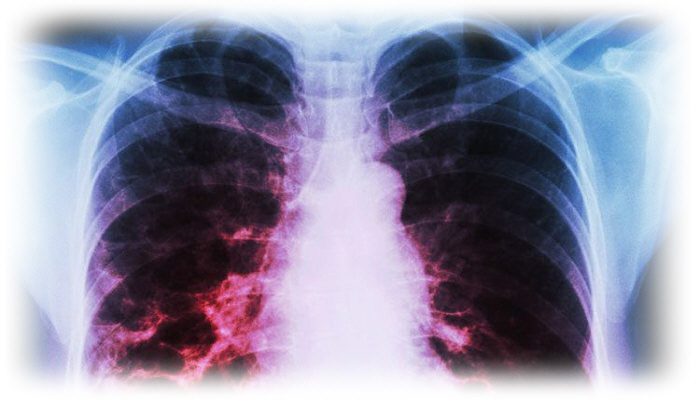

☑ حالة الكحة لازمتك من ثلاثة إلى أربعة أسابيع كاملة

☑ تصاب برعشة خلال الليل مع تصبب العرق

☑ إحساس بألم فى الصدر عند الكحة أو عندما تأخذ نفسا عميقا

☑ أنت تدخن بشراهة